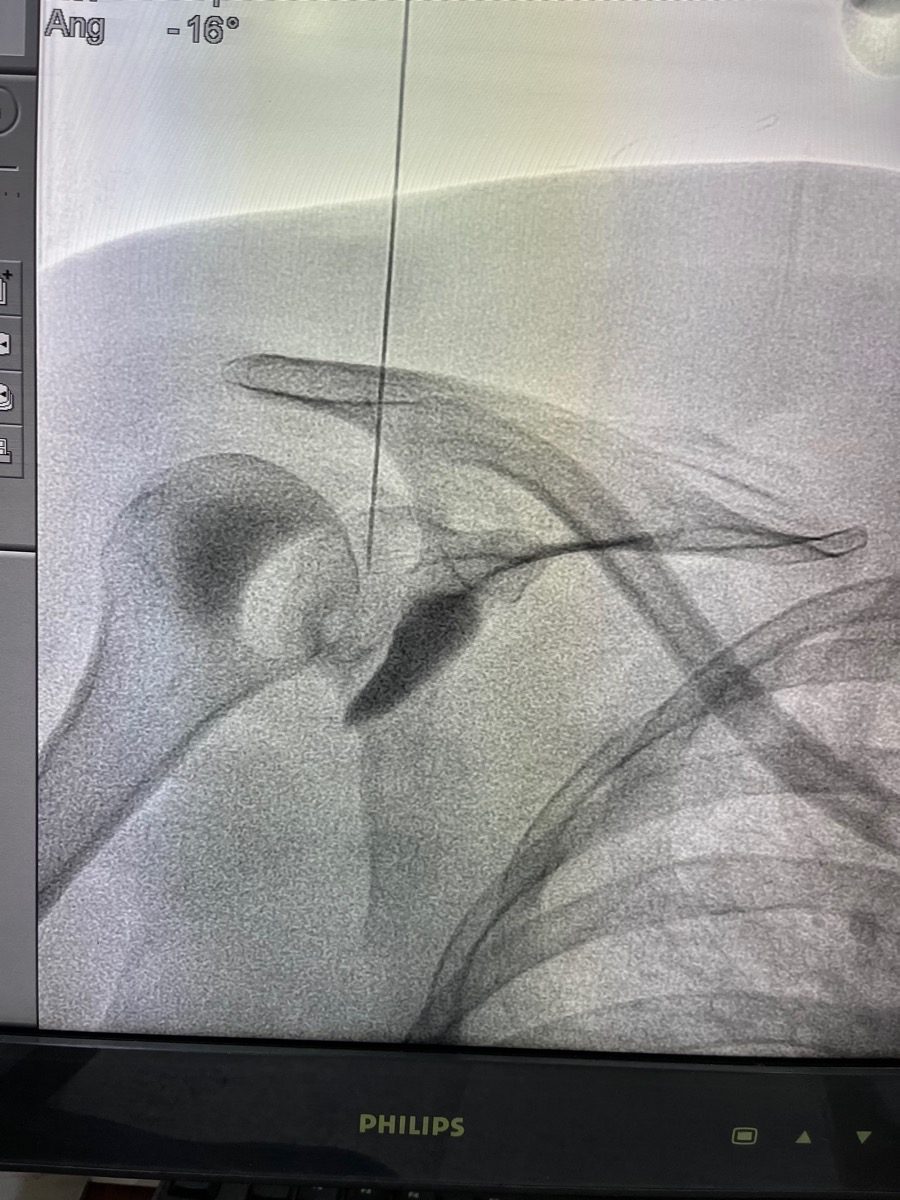

RFA: You sit or lie on your side. The procedure can be done under ultrasound or fluoroscopic guidance. RF probes are placed at the articular branches of the suprascapular and axillary nerves. A sensory stimulation test confirms positioning, then RF energy is applied to each probe site. Takes about 20–30 minutes.

Frozen Shoulder Release: Under ultrasound guidance, a needle is placed into the glenohumeral joint through the posterior approach. A 20–40 ml solution of saline, steroid, and local anaesthetic is injected slowly under pressure. You hear or feel a "give" as the capsule distends, this signals a successful release. Takes about 15–20 minutes.